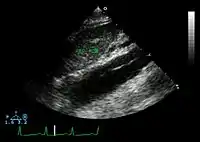

Ultrasound

An echocardiogram displaying the true lumen and false lumen of an aortic dissection: In the image to the left, the intimal flap can be seen separating the two lumens. In the image to the right, color flow during ventricular systole suggests that the upper lumen is the true lumen.

The transesophageal echocardiogram (TEE) is a good test in the diagnosis of aortic dissection, with a sensitivity up to 98% and a specificity up to 97%. It has become the preferred imaging modality for suspected aortic dissection. It is a relatively noninvasive test, requiring the individual to swallow the echocardiography probe. It is especially good in the evaluation of AI in the setting of ascending aortic dissection and to determine whether the ostia (origins) of the coronary arteries are involved. While many institutions give sedation during transesophageal echocardiography for added patient comfort, it can be performed in cooperative individuals without the use of sedation. Disadvantages of TEE include the inability to visualize the distal ascending aorta (the beginning of the aortic arch), and the descending abdominal aorta that lies below the stomach. A TEE may be technically difficult to perform in individuals with esophageal strictures or varices.